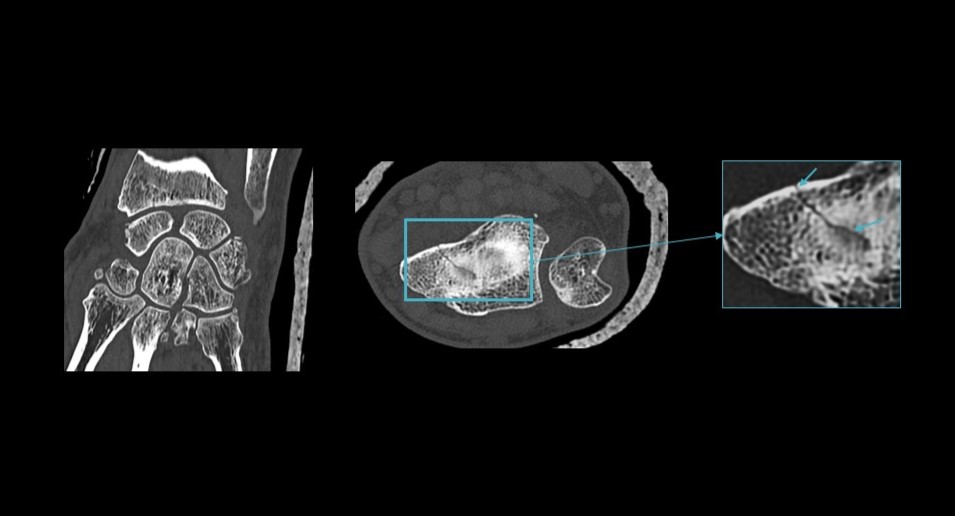

The solution uses a dedicated neural network to improve spatial resolution and reduce image artifacts, enabling clearer and more detailed CT scans. It supports imaging across areas such as lung, musculoskeletal, and inner ear diagnostics, where high-resolution visualization is critical.

The technology also supports high-resolution imaging with a 1024 matrix and enables faster scan times, including chest imaging in under one second.